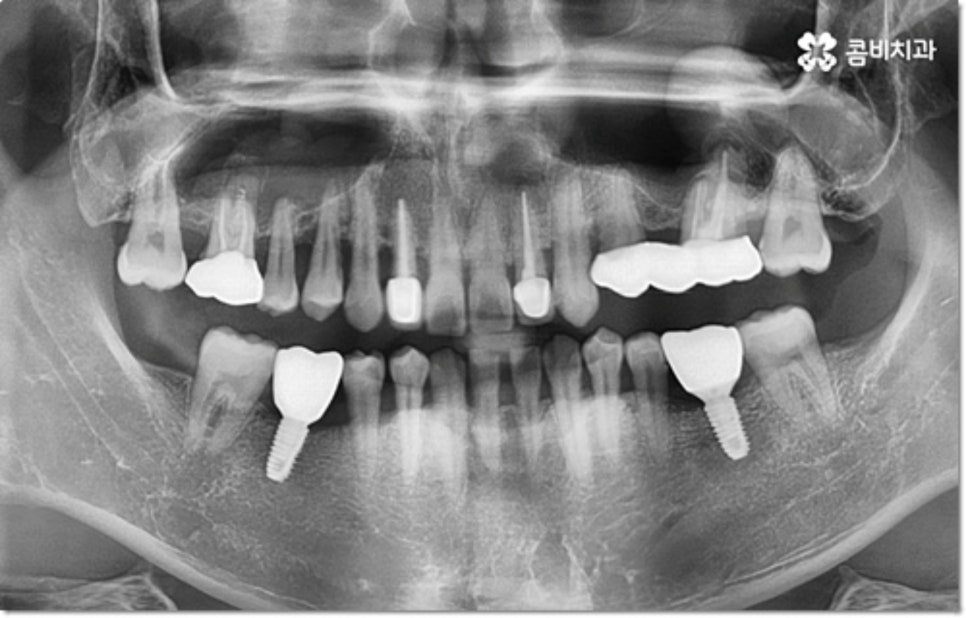

사진에서 볼 수 있는 사례는 아랫니가 크게 부러져서 빠졌을 때 아랫니임플란트 시술을 통해 수복을 해 준 거예요. 이때 빠른 일상 복귀를 원하는 만큼 기간이 얼마나 오래 걸리는가 하는 것은 임플란트 시술을 받으시는 분들의 가장 주된 관심사 중 하나라고 할 수 있는데요.

임플란트 시술 기간은 환자분들의 상황에 따라 달라지는 것이지만 보통 빠르면 36개월, 뼈이식이나 상악동 거상술과 같은 선처치가 필요한 경우 또는 회복 기간이 생각보다 오래 걸리는 경우에는 8개월1년 넘게 까지도 걸릴 수 있습니다. 혹시 모를 부작용으로 재시술을 받게 되는 경우도 있기 때문에 치과를 선택하실 때 말씀드린 의료진의 숙련도 외에도 여러 가지 사항들을 꼼꼼하게 따져보실 필요가 있어요. 3D CT 와 같은 정밀 장비로 환자분들의 잇몸 상황 또는 교합 등을 세밀하게 살펴보고 그에 맞춰 무리하지 않게 임플란트 식립을 진행하는 치과에서 검진부터 사후관리까지 체계적으로 케어받는 것이 중요한 거예요.